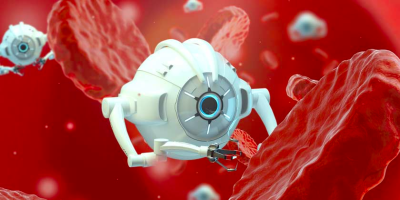

Nanobots To Avoid Potential Root Canal Failure

Nanobots are small enough to fit through the dentinal tubules in order to reach the bacteria and ...